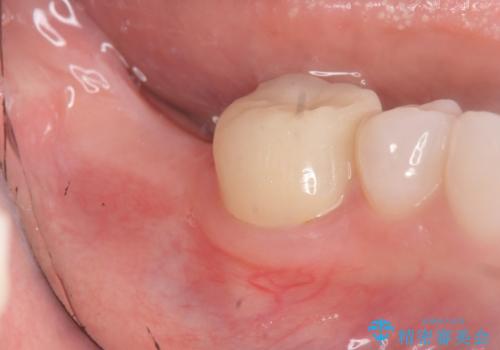

奥歯のインプラント治療

- 右下の奥歯を虫歯で喪失しそれ以来よく物が噛めず、改善を求めて来院されました。

入れ歯かインプラント治療のご提案を行い、よりしっかりとかめるインプラント治療を希望されました。

骨との結合する期間が早く、大きな咬合力にもしっかりと耐えることのできるストローマンインプラントを用いた咬合機能回復を計画します。

- 44万円(ストローマンインプラント・チタンカスタムアバットメント・仮歯・フルジルコニアクラウン)費用は治療当時の料金となります